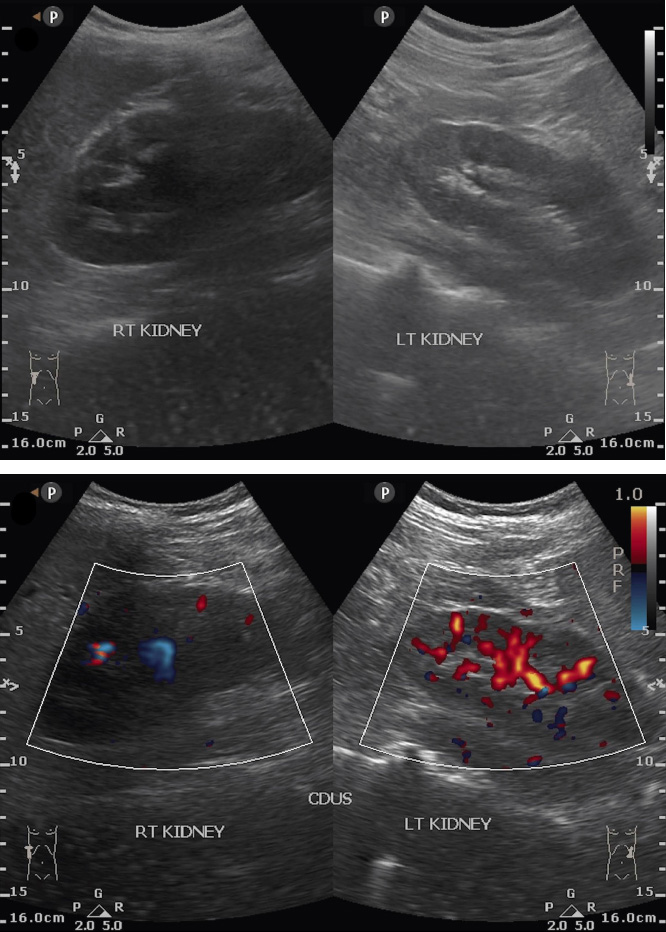

[Electronic Publication Date: September 25, 2025]Karthigesu Aimanan, Putera Mas Pian, Chew Loon Guan and Hafizan Tajri